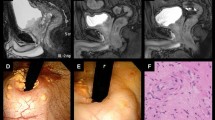

In total, 253 consecutive patients with prostate cancer treated with CIRT at KCC between December 2015 and December 2017 were analyzed in the present study. Clinical records were collected in April 2020. The eligibility criteria for this study were as follows: (i) histological diagnosis of prostate adenocarcinoma, (ii) cT1bN0M0 to T3bN0M0 according to the 7th UICC classification, (iii) performance status of 0–2, (iv) age of 20 years or older, and (v) no previous treatment for prostate cancer excluding androgen deprivation therapy (ADT). The patients were classified using the D’Amico risk group classification [21]. The study was approved by the institutional review board of KCC (approval number: 2019–145). Written informed consent was obtained from all patients.

Patients were placed in the supine position. The patients were positioned on a vacuum mattress (BlueBAG: Elekta AB, Stockholm, Sweden) and immobilized using thermoplastic shells (Shellfitter: Kuraray, Tokyo, Japan). Enema was used before computed tomography (CT) for CIRT planning. The rectum was emptied as much as possible using a laxative and antiflatulent before each session, and enema was performed if the patient did not defecate within 24 h of treatment. The patients urinated and watered 60 min before CT. A set of CT images with 2 mm-thick slices was taken for treatment planning.

The gross tumor volume was not defined. The clinical target volume (CTV) included the entire prostate and proximal seminal vesicles. In the case of T3b prostate cancer, the ipsilateral seminal vesicles were included in the CTV [22]. Prophylactic pelvic lymph node area was not included in the CTV [23]. Planning target volume (PTV) 1 was created by adding anterior and lateral margins of 10 mm and a posterior margin of 5 mm to the CTV. Boost therapy was performed using PTV2, in which the posterior edge was set in front of the anterior wall of the rectum to reduce the rectal dose in the ninth course of the treatment [24, 25]. The rectum was delineated as the organ at risk from 10 mm above the upper margin of the PTV to 10 mm below the lower margin of the PTV.